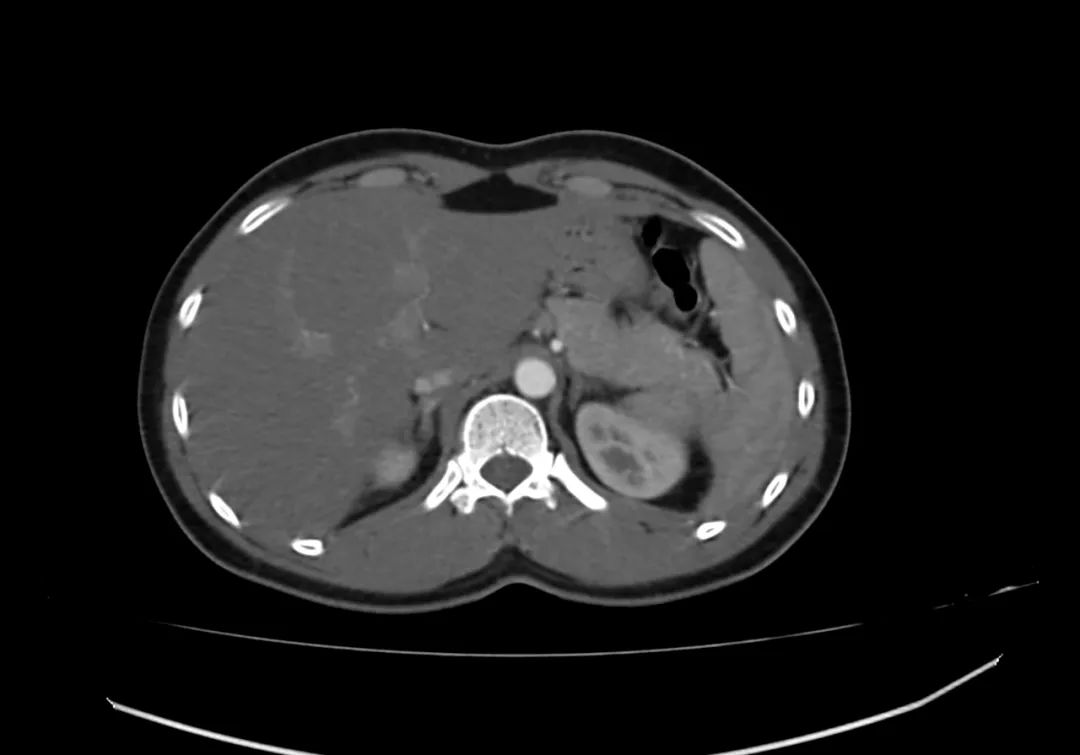

动脉期上腹部轴向增强图像显示胰腺完全包围十二指肠第二部,与完全性环状胰腺一致。

CASE M25 上腹痛 Case contributed by Dr Vinay V Belaval